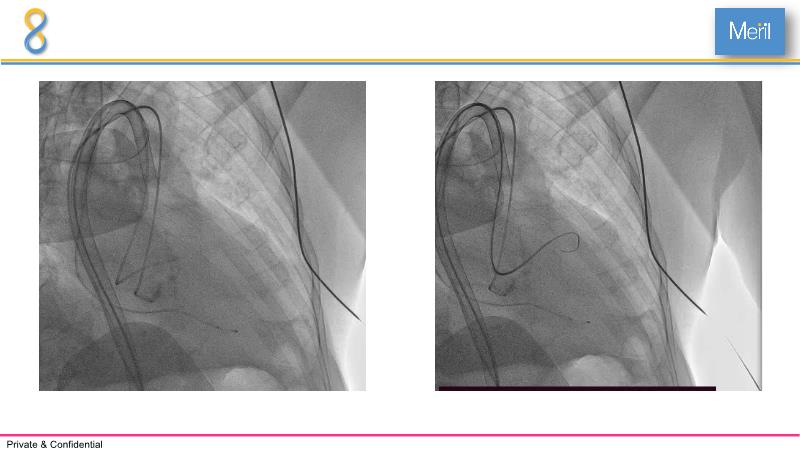

Through the presentation of several compelling cases, including an 88-year-old male with CKD, RBBB, moderate LV dysfunction, and severe aortic stenosis, a Type 1a bicuspid native AS, and an extraordinary TAVI in an 83-year-old with acute heart failure and comorbidities, this session will dive into the Myval Octapro THV. Learn about its key features, procedural impact, and potential clinical benefits. Discover the Octalign technique for predictable and precise commissural and coronary alignment, preserving coronary access. Gain insights into precise sizing, positioning, and deployment of the Myval THV series in real-world scenarios, and explore the relevance of pivotal Landmark RCTs in clinical practice.

- To know the Octalign technique which enables predictable and precise commissural and coronary alignment thus preserving coronary access

- To understand the technique of precise sizing, positioning and deployment of Myval THV series in real world clinical scenarios